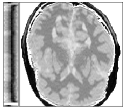

Figure 6 shows examples of the quantitative (magnitude) images of three of the 112 simulated inversion recovery measurements in the test dataset. We also show the regularization parameter-maps for regularization along the spatial directions and along the inversion-time direction generated by the network. The mean PSNR and SSIM of our proposed method is consistently higher for all considered acceleration factors, even compared to PDHG with regularization strength along spatial and inversion-time direction chosen by grid-search with access to the ground truth images (shown in Figure 8 and Table 2). The resulting parameter-maps after performing the regression on the reconstructed images are shown in Figure 7. Again, our proposed method results in the lowest RMS deviation from the ground truth images (Table 2).

CG-SENSE PDHG PDHG PDHG Target/ZF /

Example 1

Example 2

Example 3

CG-SENSE PDHG PDHG PDHG Ground Truth